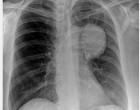

Egy férfi, akinek tüdőrákja volt és 1971. március 5-én

műtőasztalra került.

A műtétre nem került sor, mert az orvosok úgy találták, hogy

nagyon szétterjedt a rák és reménytelen a gyógyulás.

A férfi április 5-én hallott a spárga kúráról és azonnal

elkezdte alkalmazni. Augusztusra a röntgenképen semmi nyoma nem volt a

rákos megbetegedésnek.